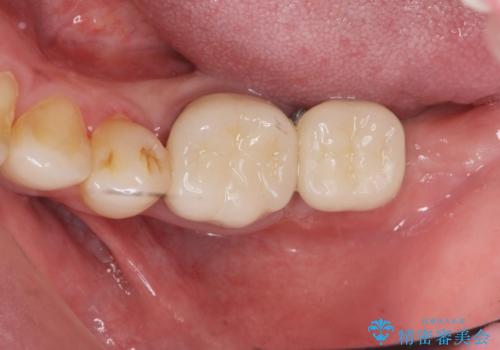

不適合ブリッジの除去 インプラントによる咬合再構成

- 保険治療を繰り返し、口腔内全体の長期的な予後に不安があり全体的な治療を希望され来院されました。

左下には親知らずを支台とした設計に無理のあるブリッジが装着されており、根管治療も不十分な状態です。

清掃性の悪いブリッジ・親知らずを除去し再根管治療・インプラントを含めた咬合再構成の計画を立てます。

設計に無理のある補綴(今回は親知らずを用いたブリッジ)は、プラークの堆積を起こしやすく虫歯や歯周病などのちに大きな問題を起こす原因となりえます。

掃除のしやすい環境を整えることで咬合機能・清掃性を改善することができます。